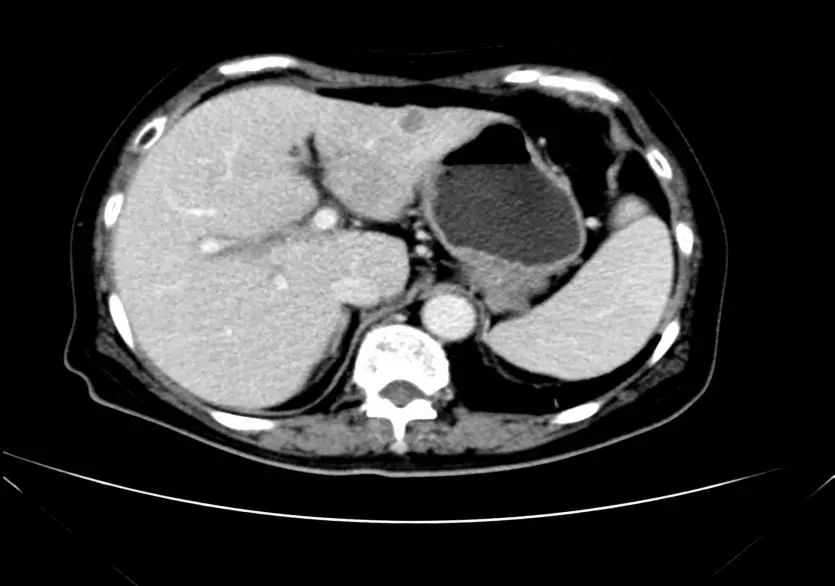

疗效评估:cPR

TOGA研究是第一个使用HER2抑制剂曲妥珠单抗治疗不能手术的局部晚期、复发或转移的HER2阳性胃癌患者的Ⅲ期临床研究。TOGA研究结果显示,IHC2+/FISH阳性或者IHC3+的患者与对照组相比,OS分别为16.0个月和11.8个月(HR为0.65)。曲妥珠单抗联合化疗显著提高了HER2阳性晚期转移性胃癌的治疗缓解率和总体生存率。2012年8月,曲妥珠单抗治疗HER2阳性转移性胃癌适应症在我国获批。对该患者进行病理切片会诊,幸运的是其HER2检测为阳性。随即进行靶向联合化疗治疗,三个周期后,肝转移灶消失,曲妥珠单抗治疗效果显著。九个周期的靶向治疗联合放化疗后,疗效评估cPR,随即行手术治疗。